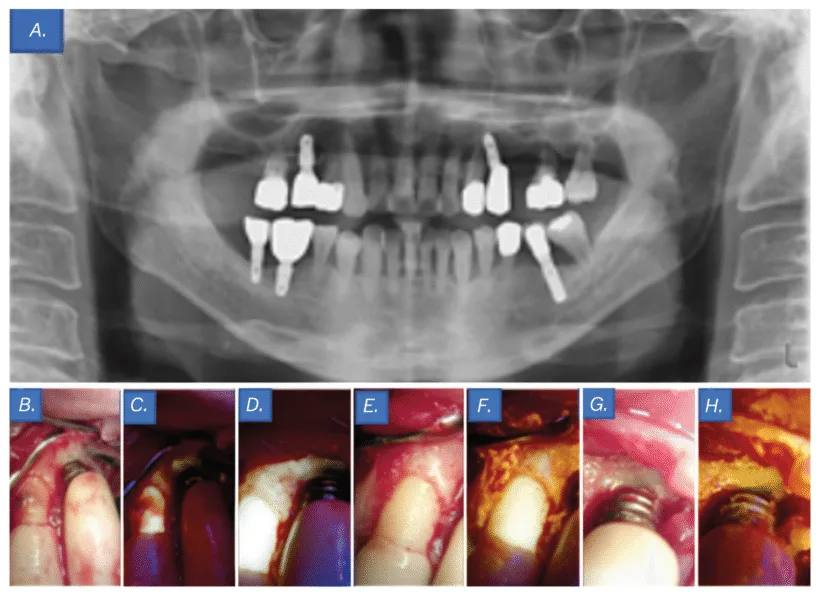

Scientific examination revealed a subgingival calculus at website tooth No. 11 and a probing depth of 6 mm at website implant No. 12. Moreover, primarily based on the panoramic radiography findings, the prognosis of tooth No. 14 was hopeless (Determine 6A); due to this fact, extraction of tooth No. 14 and flap surgical procedure for implant No. 12 have been deliberate. An intrasulcular incision was constructed from the mesial line angle of tooth No. 10 to the distal side of implant No. 12 utilizing #15T and #12 blades. After flap elevation, subgingival calculus and bone loss have been confirmed round tooth No. 11 and implant No. 12, respectively (Determine 6B).

Though no biofilm was seen to the bare eye on the implant No. 12 threads, QLF imaging revealed its presence (Determine 6C). Biofilm elimination was carried out utilizing an ultrasonic scaler (Megagen, Seoul, South Korea), curette, and microbrush. Comply with-up QLF imaging was performed to judge the pre- and post-treatment distinction, confirming profitable biofilm elimination (Determine 6D). The realm was irrigated with tetracycline, and extra medical pictures and QLF photographs have been taken to confirm the elimination of biofilm and an infection at tooth No. 11 and implant No. 12 (Figures 6E-6H). Interrupted sutures have been positioned utilizing 4-0 absorbable artificial sutures (Coated Vicryl™, Ethicon, Johnson & Johnson, Somerville, USA). The significance of oral hygiene administration was emphasised utilizing visible aids, and tooth brushing instruction (TBI) was offered.

One week after the flap surgical procedure and implant floor decontamination, the affected person returned for suture elimination and reported vital reduction from discomfort. Therapeutic was uneventful, with no notable issues.

On the 6-month follow-up go to, the affected person’s medical signs had resolved. By way of common TBI, implant floor hygiene had improved in comparison with the pre-treatment situation, and the general oral well being remained secure.